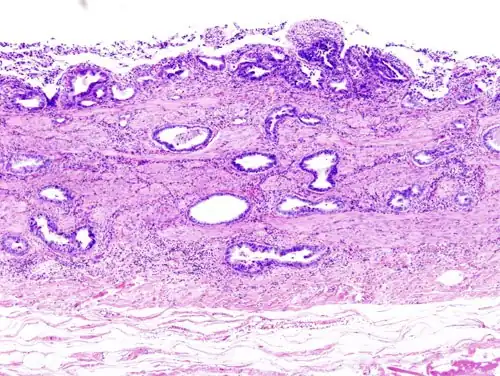

Incidentally discovered gallbladder cancer (adenocarcinoma) following a cholecystectomy. -

Gallbladder adenocarcinoma histopathology